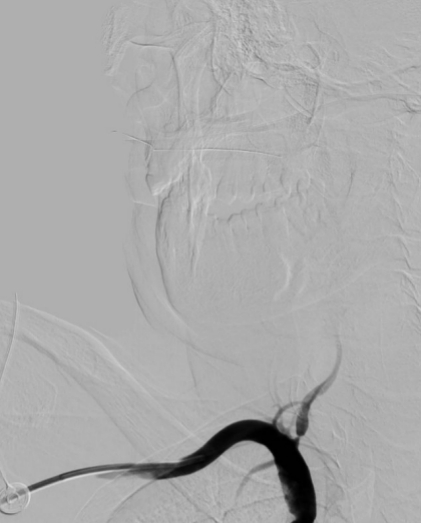

图片4.jpg

椎动脉狭窄                                                  椎动脉支架术后〔经桡动脉入路〕